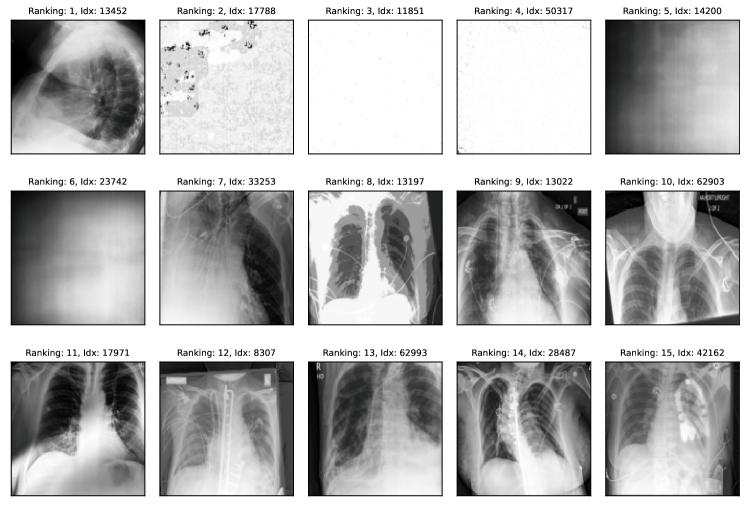

Natural experiment setup. To further validate the proposed approach, we evaluate it on data quality issues naturally found in benchmark datasets. To this end, we devise two different experiments. In the first experiment, we measure how well the ranking matches available metadata, e.g. if two images show the same person or if the label was obtained using gold-standard tools in medical diagnosis. This experiment is, however, specific to each dataset depending on the applicability of the available metadata. Therefore, in a second experiment, we use SelfClean to propose a ranking for some datasets and gather partial human annotations for validation. We collect annotations from medical experts for the medical datasets and rely on crowd workers for general image datasets. We then evaluate the proposed ranking using human annotations as described in appendix I.

Comparison with human annotators. We evaluate SelfClean rankings based on human annotations across two medical and two common vision benchmarks as described in appendix I. The evaluation reveals that images ranked by SelfClean as the most likely to contain data quality issues are also identified by human experts as problematic significantly more often than random images. As shown in table 8, we find 95% significant differences in nine of twelve evaluations for comparing the lowest 50 ranked images to a random selection and six of ten evaluations for comparing images ranked 1-25 to images ranked 26-50. Two cases in the second comparison are excluded because too many positive samples give undefined metrics. Results indicate that the proposed ranking, to a large degree, coincides with human understanding of these three noise types. Therefore using SelfClean can increase efficiency when analyzing and fixing data quality issues.